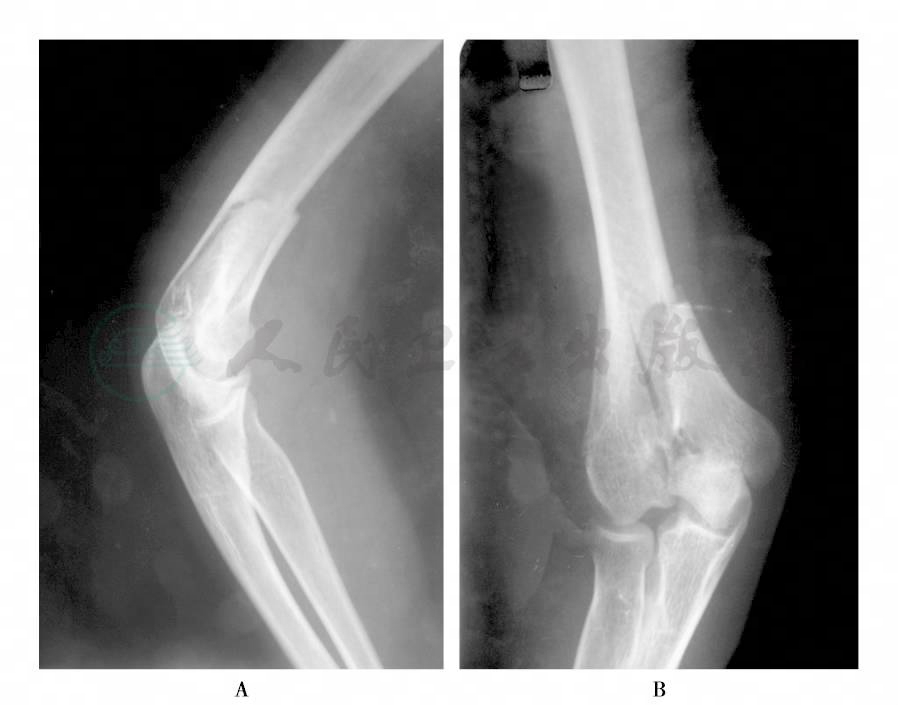

右肘关节正、侧位X线片:右肱骨髁间骨折伴内侧髁移位(图1)。心电图未见明显异常。

图1 右肱骨髁间骨折伴内侧髁移位X线片

A.侧位;B.正位